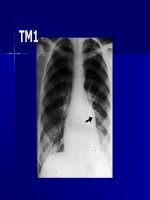

SỰ LÃO HÓA Ở TIM:

2. Thay đổi ở cấu trúc tim

•Khối cơ: ở nữ giới, gia tăng theo tuổi.

• Khối cơ thất trái: 15% từ 30 tới 70 tuổi.

•Sự dày của thành thất: vách liên thất,

thành tự do thất trái.

Kích thước buồng tim:

• kích thước nhĩ trái ở người khơng có

bệnh tim từ 30 đến 70 tuổi.

• Hậu quả: rung nhĩ.

NC CHS (Cardiolvascular Health Study)